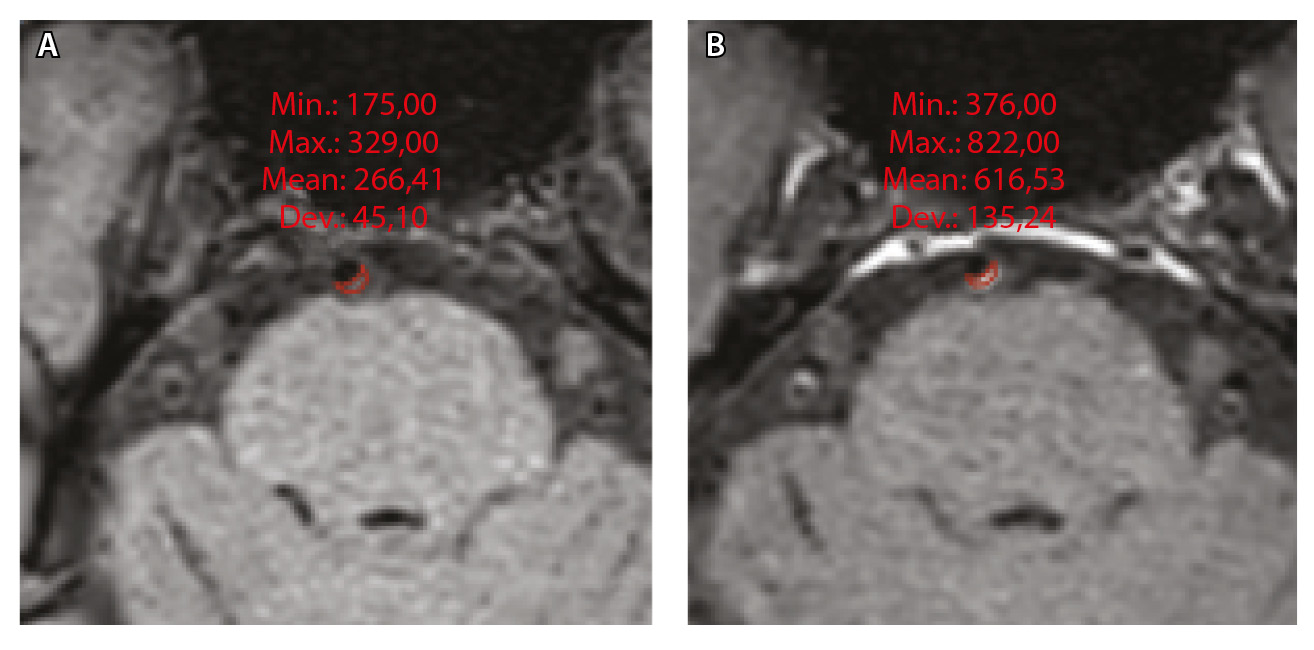

где WEI (wall enhancement index) – индекс усиления контрастности стенки (сосудов), SIwallprecontrast – интенсивность сигнала (Signal Intensity, SI) сосудистой стенки (wall) в зоне интереса на преконтрастных (precontrast) изображениях, SIwallpostcontrast – интенсивность сосудистой стенки в зоне интереса на постконтрастных (postcontrast) изображениях; SIbrainprecontrast – интенсивность неизмененного белого вещества мозга (brain) на доконтрастных изображениях; SIbrainpostcontrast – интенсивность неизмененного белого вещества мозга на постконтрастных изображениях. Пример измерения интенсивности сигнала от АСБ для расчета WEI приведен на рисунке 1.

Рис. 1. Пример измерения интенсивности эхо-сигнала от атеросклеротической бляшки базилярной артерии для расчета индекса усиления контрастности стенки сосуда (WEI). В месте максимального стеноза артерии на одном срезе отмечали область интереса (ROI) и регистрировали среднее значение интенсивности сигнала от сосудистой стенки (SIwall). ROI были сопоставлены по размеру и местоположению в наборе данных T1-TSE-db-FS до (А) и после (Б) контрастного усиления; макс. – максимум, мин. – минимум, откл. – отклонение, средн. – среднее